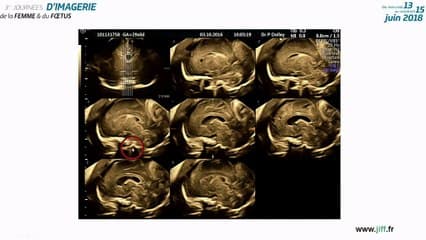

Pour faciliter l’analyse du coeur foetale a l’echographie du T2, surtout en cas d’obesite maternelle ou du foetus en position difficile, il faut optimiser les reglages, tourner autour du foetus . Il faut surtout analyser les elements du coeur normal : coupe quatre cavites, coupe Vg-aorte, coupe coeur droit et trois vaisseaux. En partant du coupe du coeur normal, on nous presentent des cas de „faux” ou vrai CIV, Cia, hypotrophie du coeur gauche comme signe d’appel de la T21, diverticule de la pointe du Vd comme variante du coeur normal, malalignement des valves auriculoventriculaire. A vos echographes!

Brillante démonstration de JM LEVAILLANT sur l'apport du 3D dans un premier temps en pathologie gynécologique avec de belles images malformations utérines (cloison, bicorne etc...) de fibromes avec leur localisation précise, d'hystérosonographie, d'injection dans les trompes, l'aspect des ovaires (OPK, cancer de l'ovaire) et des malformations fœtales très richement iconographiées. On est convaincu !